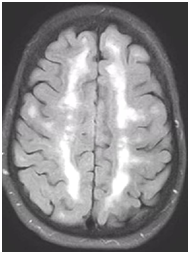

During follow-up in stroke clinic, her imaging was reviewed. MR imaging demonstrated large confluent areas of hyperintense T2 and FLAIR signal abnormality throughout the periventricular and deep white matter with extension into the subcortical white matter (Figure 1) (Figure 2). T1w images demonstrated low signal, corresponding to the T2/FLAIR abnormality on T2w images. This white matter abnormality is known as leukoaraiosis. The hyperintense T2/FLAIR signal abnormality also involved the anterior temporal lobes (Figure 3) (Figure 4) and external capsules (Figure 5) (Figure 6). This feature on MRI is uncharacteristic of other white matter diseases, notably the sporadic subcortical atherosclerotic encephalopathy. In our patient, the corpus callosum was spared. The lacunar infarcts were small vessel infarcts, typically seen in the deep white matter, basal ganglia, thalami, and the pons. On diffusion images, there was a small area of diffusion restriction in the left corona radiata that was consistent with an acute infarct (Figure 7) (Figure 8). Subsequently, there was an area of encephalomalacia on follow-up MRI at the location of the previous acute infarct. This abnormality correlated with the right-sided weakness seen prior to the index patient’s admission.

Figure 5 Relatively symmetric hyperintense T2 signal involving the external capsules, on both sides.

Figure 6 Axial FLAIR image demonstrates relatively symmetric hyperintense signal in external capsules on both sides.

The white matter signal abnormality is nonspecific and seen in many diseases. However, the involvement of the anterior temporal lobes (86%) and external capsules (93%) is specific to suggest the diagnosis of CADASIL in appropriate clinical settings.8,9 CADASIL is a rare entity, its clinical features are nonspecific, and it is almost never considered as a leading differential at first presentation. However, MRI findings are relatively specific in the early course of the disease. MRI helps to rule out large territory infarctions and major intracranial or neck vessel occlusions. It also differentiates other conditions such as mitochondrialencephalopathy and stroke like episodes (MELAS), migraine disorders, and demyelinating disease like multiple sclerosis. Early involvement of the anterior temporal lobes and external capsules is characteristic in the initial stages of CADASIL. As the disease progresses, there is involvement of the white matter, which can also be seen with advanced demyelinating disease and microangiopathy. Hence, radiologists should be aware of the characteristic MR findings and clinical features as it guides the clinician to genetic testing for the specific diagnosis of the CADASIL.10